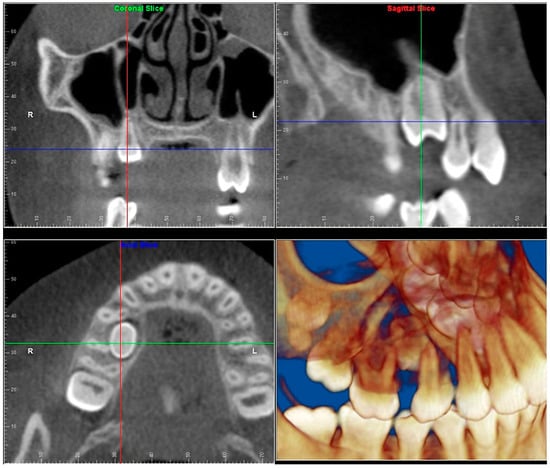

- Evaluation of impacted teeth, a common indication of CBCT in orthodontics. The advantages of CBCT include assessment of the tooth location and position, the stage of development, and status of adjacent teeth. CBCT is justified in these cases, because CBCT has the capability of evaluating the impacted teeth and adjacent structures more accurately than 2D conventional imaging. The benefit–risk ratio is favorable, especially if the CBCT volume is collimated to the impacted tooth. Figure 1, Figure 2, Figure 3 and Figure 4 show an example of impacted maxillary canines, and their proximity to the maxillary lateral incisors. Figure 1 shows an intraoral photograph. The benefit of CBCT acquisition in this case includes the ability to visualize the canines and the lateral incisors in three dimensions, which can be visualized in Figure 2 and Figure 3. In this case, the maxillary right lateral incisor exhibited external root resorption, a finding that would be difficult to see on a conventional 2D panoramic radiograph. Figure 4 shows a Maximum Intensity Projection of a panoramic view derived from the CBCT volume. This unique view is free of magnification, distortion, ghost images, and overlaps frequently seen in conventional 2D panoramic radiography.